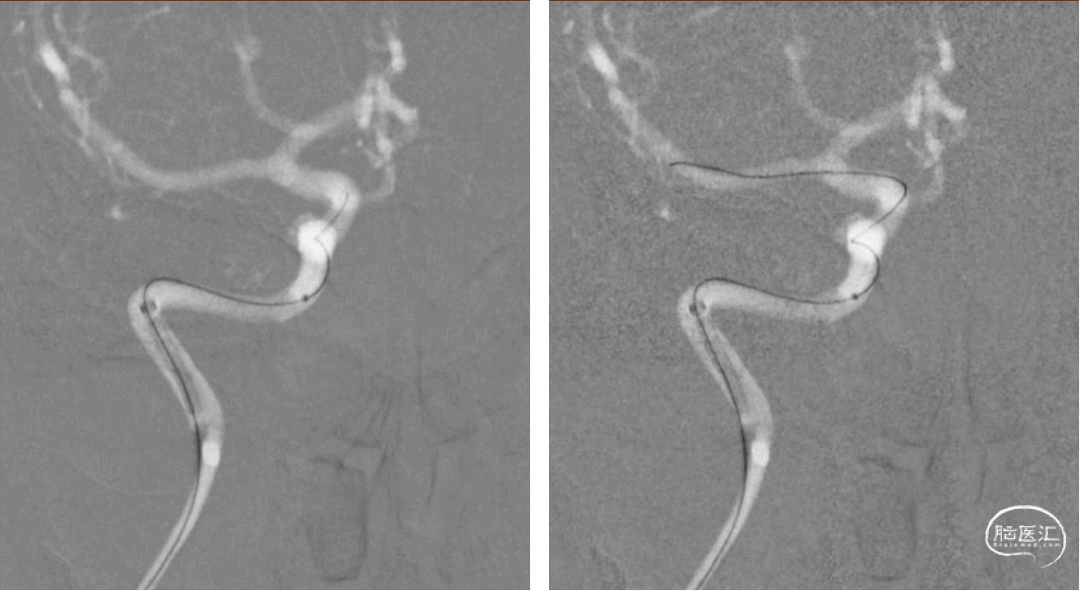

此次住院,造影显示动脉瘤增大且伴有子囊,瘤体4.6mm*3.1mm,瘤体最大径5.1mm,瘤颈宽4.6mm,为宽颈动脉瘤。

术前测量:瘤体4.6mm*3.1mm, 瘤颈宽4.6mm,近端血管直径4.7mm,选择4.75mm*20mm Pipeline。

送入4.75mm*20mm PED密网支架。

逐步推挤释放支架。

根据造影定位,继续释放支架。

继续释放。

释放完毕,回收输送系统,释放过程中,通桥银蛇®DA提供稳定支撑,几乎不移位。

密网支架释放完后常规按摩,以促进更好贴壁。

近端按摩完毕后,复查3D旋转造影。

稀释造影及融合后提示PED贴壁良好。